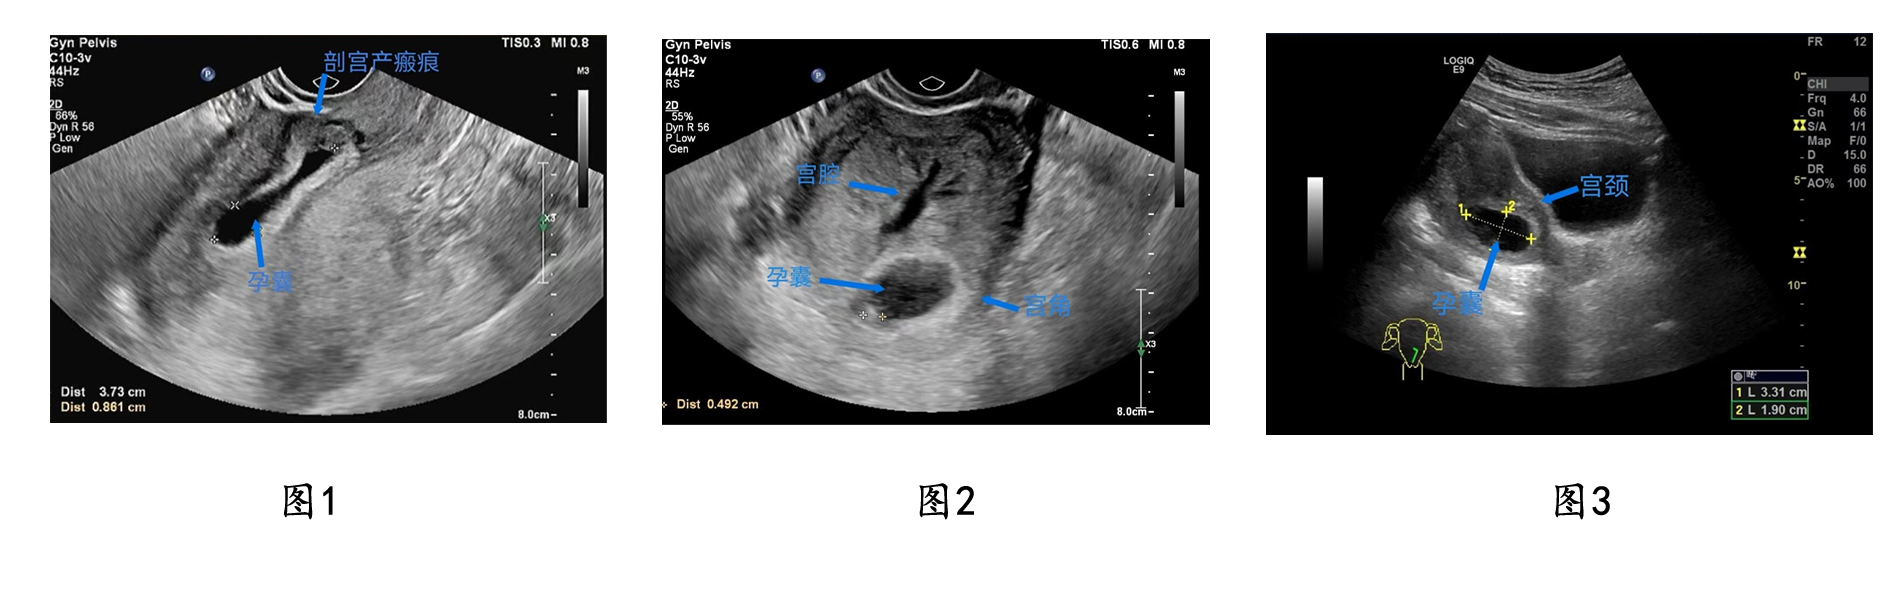

最近一个多月,东院妇科连续接诊了几例异位妊娠的高危患者,包括剖宫产瘢痕妊娠(见图1);妊娠囊着床于子宫角的“宫角妊娠”(见图2);妊娠囊着床于宫颈管的“宫颈妊娠”(见图3)等。